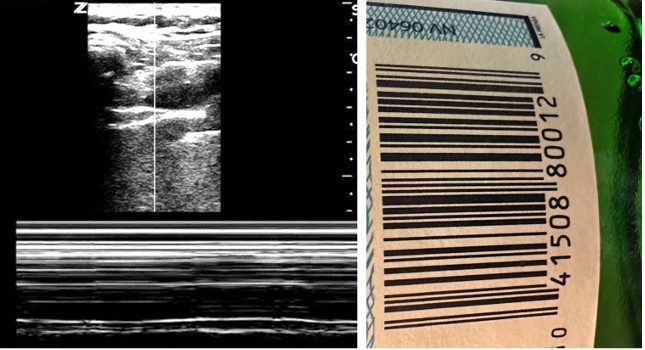

- Stratosphere sign: A barcode-like pattern indicating absent pleural sliding, consistent with pneumothorax. You can artificially create this in a normal patient by asking the patient to stop breathing.

Figure 4. Pneumothorax – Stratosphere sign or Barcode sign (M-mode). Observe that the barcode sign on the left is very similar to the barcode on a product (right).